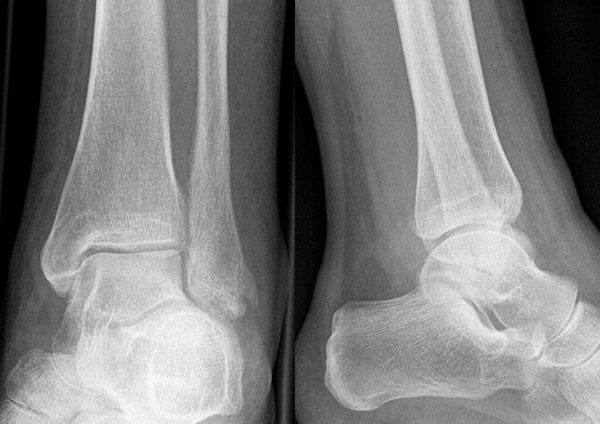

Luxationsfrakturen (Abbildung 7) sollten unter i.v.-Analgesie so schnell wie möglich reponiert werden, um Haut- und Weichteilschäden, Störungen der Durchblutung und Sensibilität, sowie den durch die Fehlstellung bedingten Druck auf den Knorpel zu verringern. Anschließend erfolgt die Ruhigstellung in einem gespaltenen Unterschenkelgips. Offene Frakturen, geschlossene Frakturen mit kritischen Weichteilverhältnissen, sowie hochgradig instabile Frakturen, die sich unter entsprechender Analgesie nicht zufriedenstellend reponieren bzw. retinieren lassen, stellen eine Notfallindikation dar. In diesen Fällen sollte die Anlage eines Fixateur externe erfolgen (Abbildung 8). Die definitive Frakturversorgung erfolgt zweizeitig nach entsprechender Konsolidierung der Weichteile. Eine Kompartment-Spaltung ist bei OSG-Frakturen nur sehr selten erforderlich.

Die Standard-Röntgenaufnahmen des oberen Sprunggelenks bestehen aus drei Aufnahmen: der antero-posterioren Aufnahme (ap), der antero-posterioren Aufnahme mit Innenrotation des Unterschenkels von 20° („Mortise view“), sowie der streng seitlichen Aufnahme (siehe S2-Leitlinie Sprunggelenksfraktur). In der Röntgen-Bildgebung sollte neben den klassischen Frakturzeichen die Integrität der Syndesmose beurteilt werden. Dies erfolgt über die Beurteilung der Breite des lateralen und medialen Gelenkspalts („medial clear space“), des tibiofibularen Abstands 1cm oberhalb des OSG-Gelenkspalts („tibiofibular clear space“), bzw. der tibiofibularen Überlappung. Eine Verbreiterung des tibiofibularen Abstands über 5 mm oder die Erweiterung des medialen Gelenkspalts können Zeichen einer begleitenden Syndesmosenverletzung sein. (Abbildung 3) 6.